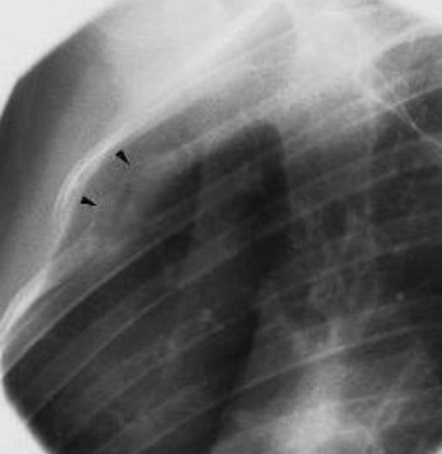

Image radiologique plain film et TDM : Aspect

radiologique plain film et TDM sur les côte du thorax est

image de destruction osseuse, permeative excentree et infiltrer

avec de bord irrégulier, Les couches de

réaction périostées créant

l'image d'une coque corticale en pelure d'oignon

,

Plus rarement, la lésion peut être avoir un caractère mixte,

c'est-à-dire lytique et sclérotique

.